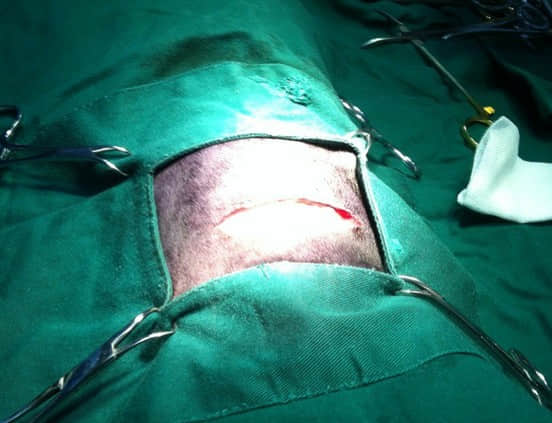

切开右侧胸部皮肤及皮下组织

手术的风险就是食道太小,可操作的范围很小,还要避开迷走神经核膈神经。手术采用左侧卧位,右侧第6和第七肋间切开,用撑开器撑开肋骨,用手指轻触食道,感知异物的位置,用两根缝线在异物两侧拉起食道,用生理盐水湿纱布隔离,切开食道,吸出食道内液体,取出异物,缝合食道,缝合胸壁,缝合胸壁时留一根管子用作抽吸胸腔空气用,缝合完胸壁抽出胸腔内气体以便形成负压,拔出管子,手术结束;讲起来很简单,做起来有难度,需要小心谨慎操作。